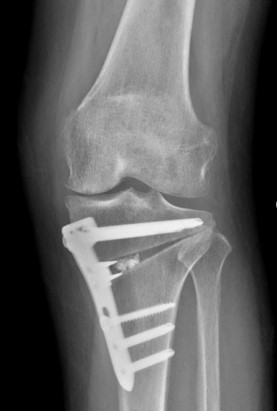

2024년 학회에서 나 교수는 “대퇴골 또는 경골 골절 부정유합에 대한 교정술”을 주제로, 휘어진 뼈로 인한 통증과 기능장애를 수술로 바로잡는 방법과 실제 임상 사례를 소개해 큰 주목을 받았습니다. 정밀한 뼈 정렬, 해부학적 복원 등 고난이도 절골술의 경험을 공유하며 현장의 의료진들로부터 깊은 인상을 남겼습니다.

2025년 학회에서는 ▲근위 경골 절골술(HTO)의 합병증을 예방하는 수술 기법 ▲외반슬(Genu Valgum)과 동반된 슬개골 탈구 환자에게 시행하는 원위대퇴골 절골술(DFO) 등 두 개의 주제로 발표를 진행하며, 보다 정교한 절골술의 접근 방법과 실제 수술 사례를 통해 학회 참가자들과 노하우를 공유했습니다.